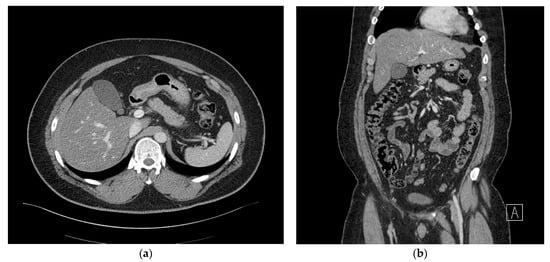

Subsequently, although the patient did not develop a fever, continued right upper abdominal mild tenderness was reported. On postoperative day 17, a follow-up abdominal CT scan was performed. which revealed a marked increase in multiple fluid collections in the right subhepatic space, measuring 135 × 105 mm, with the formation of an abscess wall, abut to the transverse colon. In addition, there was secondary inflammatory change in the colon (Figure 3a,b). At this time, the patient’s weight had reduced to 124 kg (%TWL: 9.2%, %EWL; 25.0%) and percutaneous drainage could be performed. In the pus culture, A. odontolyticus was identified. With a diagnosis of A. odontolyticus, and in consultation with the division of infectious disease, intravenous administration of 6.75 g of tazoperan per 8 h was initiated. A high dose of antibiotics was administered due to the patient’s obesity.

Figure 3. (a) Axial view of the abdominal computed tomography (CT) scan showing a marked increase in multiloculated fluid collections in the right subhepatic space. (b) Coronal view of the abdominal computed tomography (CT) scan showing multiloculated fluid collections in the right subhepatic space, abutting the transverse colon.